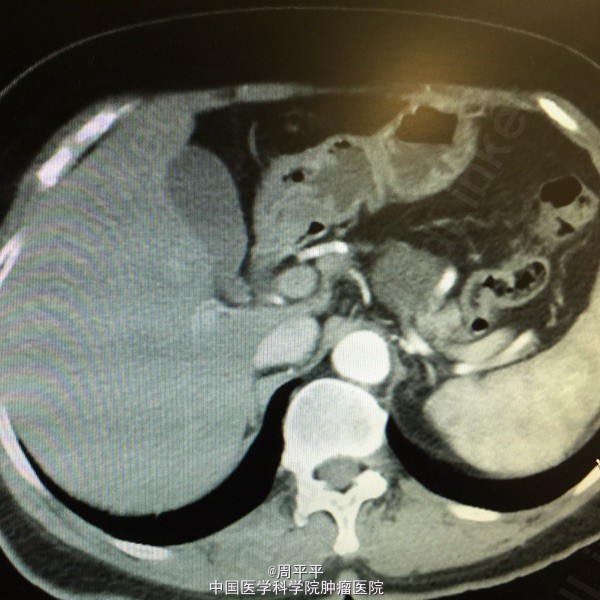

主诉:体检发现胰腺肿物18月 现病史:患者18月前因心慌不适就诊于当地医院,行腹部超声提示胰尾部囊性占位,大小约1.7×2.7cm,无腹痛、腹胀,无皮肤粘膜黄染等不适。4月前,在外院查腹部CT提示胰尾囊性肿物较前增大,约3.5×2.3cm。后于我院就诊,查血CA19-9 6.4。发病中,无腹痛、黄染等不适。体重无明显变化。 既往史:既往有频发房早,口服倍他乐克,安博诺无诉不适。

查体:全腹无压痛,未触及明显包块。 辅助检查: 腹部增强CT+三维重建:胰体部类圆形囊性密度影,大小约3.0×2.6×3.4cm,脾动、静脉受压移位。

诊断: 胰腺占位 行腹腔镜下胰体尾+脾切除。术后恢复良好。术后病理回报:胰腺粘液性囊腺瘤。

讨论:患者中老年女性,体检发现胰尾部占位,外院查腹部CT提示胰尾囊性肿物,大小约3.5×2.3cm,查血CA19-9 6.4U/ml。根据影像学检查,考虑浆液性囊腺瘤可能性大。该病为最常见的胰腺囊性肿瘤,起源于胰腺腺泡细胞,囊液清亮稀薄,富含糖原,囊壁光滑,无无恶变倾向。